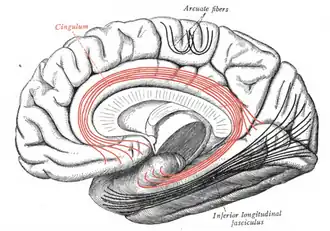

Cingulum (brain)

Medial surface of right cerebral hemisphere. Some of major association tracts are depicted. Cingulum is at center, in red. | |

In neuroanatomy, the cingulum or cingulum bundle is an association tract, a nerve tract that projects from the cingulate gyrus to the entorhinal cortex in the brain, allowing for communication between components of the limbic system.[1] It forms the white matter core of the cingulate gyrus, following it from the subcallosal gyrus of the frontal lobe beneath the rostrum of corpus callosum to the parahippocampal gyrus and uncus of the temporal lobe.[2]

The cingulum is described from various brain images as a C-shaped structure within the brain that wraps around the frontal lobe to the temporal lobe right above the corpus callosum. It is located beneath the cingulate gyrus within the medial surface of the brain therefore encircling the entire brain. There are two primary parts of the cingulate cortex: the posterior cingulate cortex and the anterior cingulate cortex. The anterior is linked to emotion, especially apathy and depression. Here function and structure changes are related meaning any change within this structure would lead to a function change, particularly behavioral because of its function involving emotions. Damage to this area can have various effects on mental disorders and mental health. The posterior section is more related to cognitive functions. This can include attention, visual and spatial skills, working memory and general memory. Because of its location, the cingulum is very important to brain structure connectivity and the integration of information that it receives.[4]